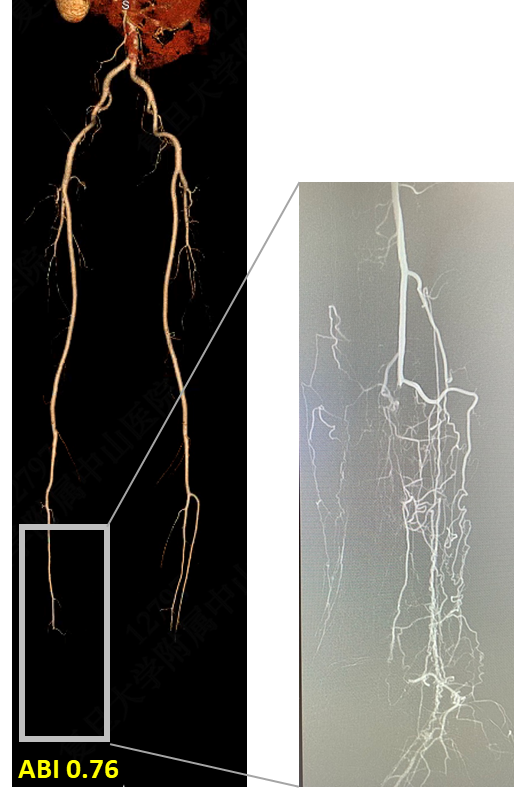

技术失败:R5 ischemia → 股总-远端胫后In-situ GSV旁路

4次EVTs反复复发:R5 ischemia → 腘P3-足背non-reversed GSV旁路

EVT后临床失败:R5 ischemia → 腘P3-足底动脉 reversed GSV旁路

307条肢体干预中,75例旁路手术经验:

总占比10%→41%

腹股沟上:24%

近端旁路:28%

远端旁路:48%

高比例R5/6、WIfI III/IV、GLASS III

腔内失效病例:63%

在deNovo病变及EVT失效病例中

膝上FPAK比例不足10%,在EVT失效病例中,膝下FPBK高达38.9%

两组中,均有高比例远端旁路(踝上及踝下):57% vs 47%